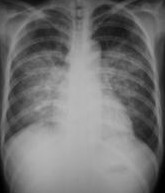

本病可严重影响呼吸功能,是临床上较常见的急性呼吸衰竭的病因。主要临床表现为极度呼吸困难,端坐呼吸,紫绀,大汗淋漓,阵发性咳嗽伴大量白色或粉红色泡沫痰,双肺布满对称性湿啰音,X线胸片可见两肺蝶形片状模糊阴影,晚期可出现休克甚至死亡。动脉血气分析早期可有低O2、低CO2分压、严重缺O2、CO2 潴留及混合性酸中毒。

肺水肿间质期的X线表现主要为肺血管纹理模糊,增多,肺门阴影不清,肺透光度降低,肺小叶间隔增宽。两下肺肋膈角区可见与胸膜垂直横向走行的KerleyB线,偶见上肺呈弧形斜向肺门较KerleyB线长的KerleyA线。肺泡水肿主要表现为腺泡状致密阴影,呈不规则相互融合的模糊阴影,弥漫分布或局限于一侧或一叶,或从肺门两侧向外扩展逐渐变淡成典型的蝴蝶状阴影。有时可伴少量胸腔积液。但肺含量增加30%以上才可出现上述表现。CT和核磁共振成像术可定量甚至区分肺充血和肺间质水肿,但费用昂贵。

- 分布和形态呈多样性,可呈中央型、弥漫型和局限型。中央型表现为两肺中内带对称分布的大片状阴影,肺门区密度较高,形如蝶翼称为蝶翼征。局限型可见于一侧或一叶,多见于右侧。除片状阴影外,还可呈一个或数个较大的圆形阴影,轮廓清楚酷似肿瘤。

- 动态变化:肺水肿最初发生在肺下部、内侧及后部,很快向肺上部、外侧及前部发展,病变常在数小时内有显著变化。